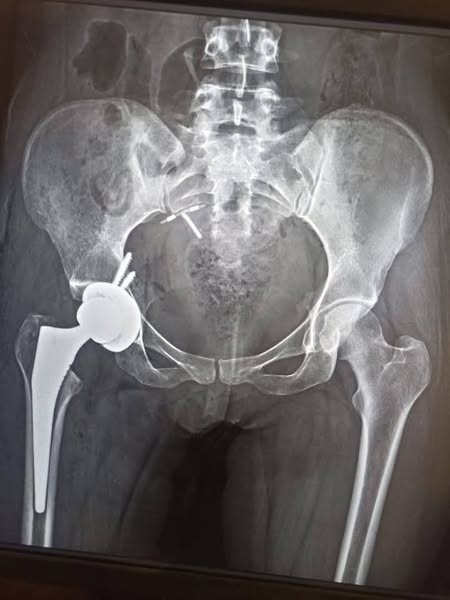

A medical team at Assiut University Trauma Hospital successfully performed a total hip replacement surgery using a cementless total hip arthroplasty using a limited anterior femoral approach for a patient suffering from hip osteoarthritis.